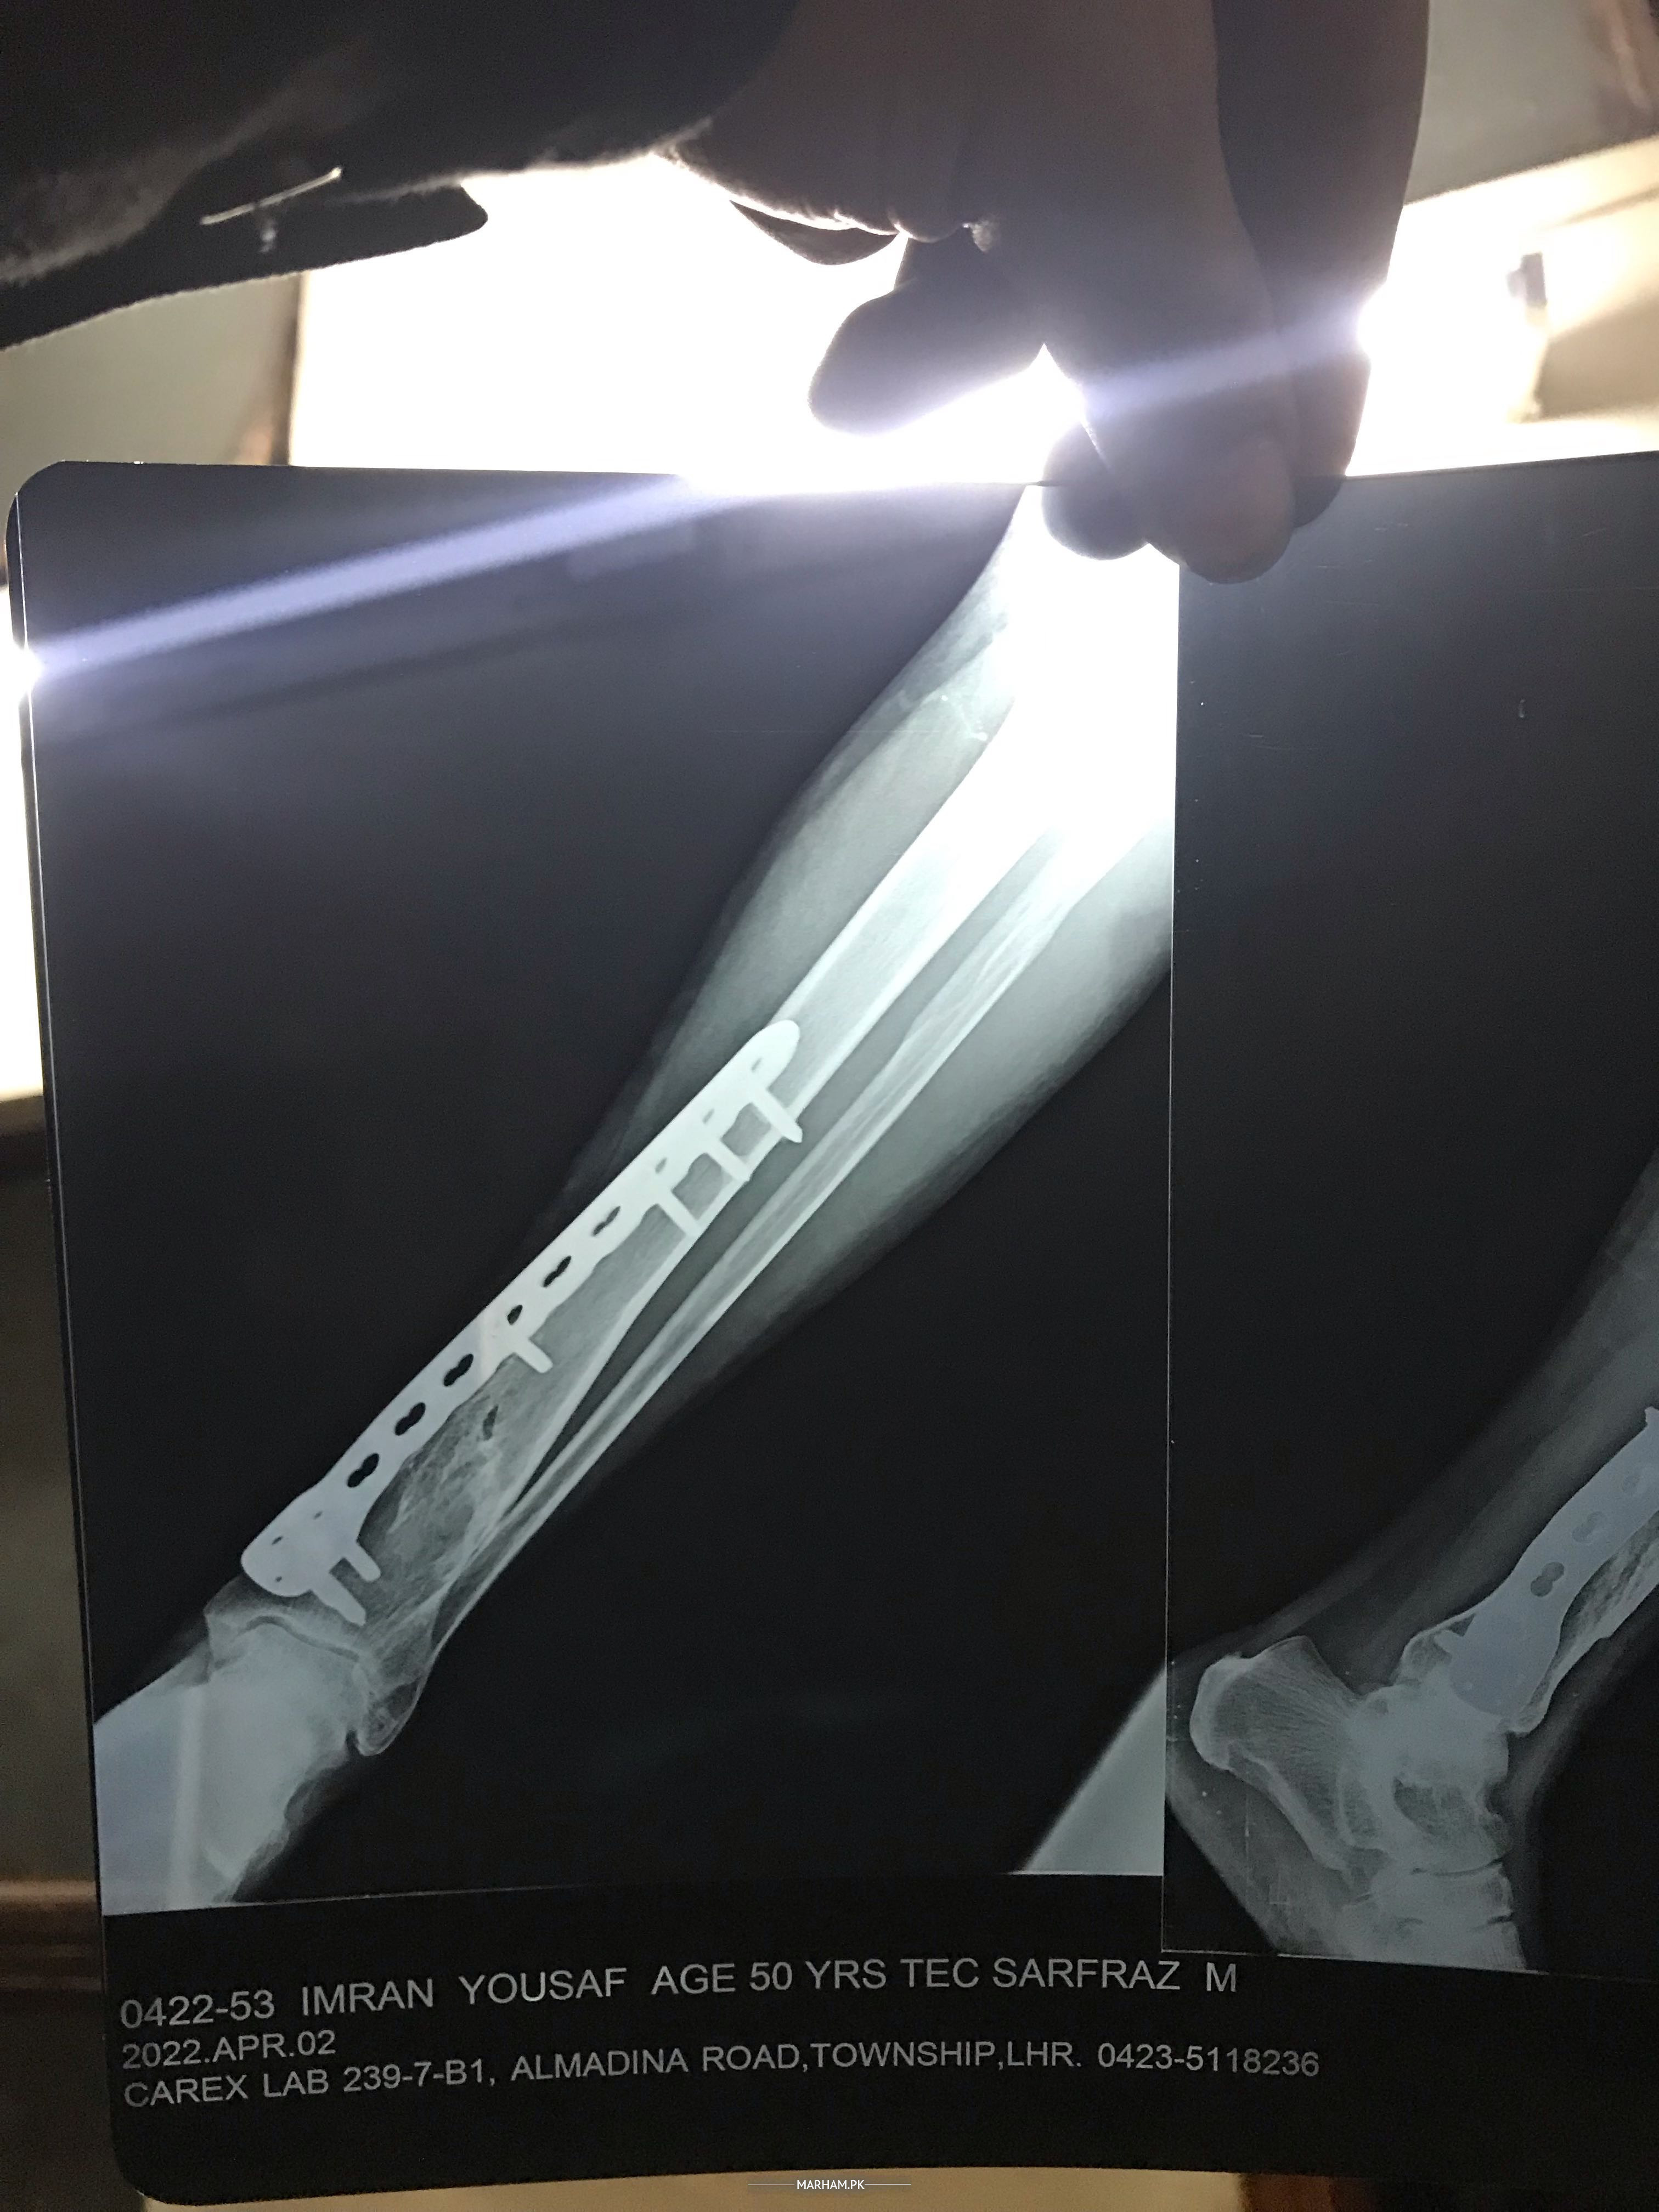

Fresh xray 2 aprail 2022

Fresh xray ha plate nikal saqti ha ab ?? Drd krti ha

x-rays tibia with Ankle and Knee

Updated x-rays required, tbhi phr plates k nikalny ya na nikalny ka faisla ho skta ha

Salam, you can get new x-ray of leg if bone has healed then plate can be removed. There will be not guarantee for pain yo be settled, however many people feel better after removal of implant. I am in Rawalpindi/Islamabad and you are welcome in my clinic. Thanks